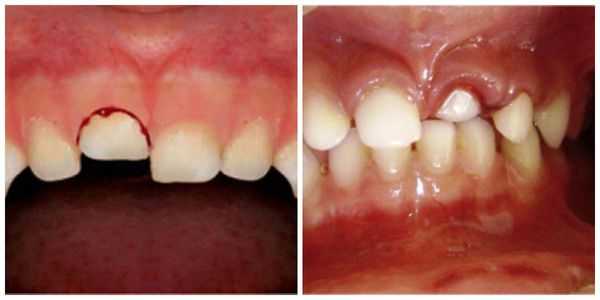

- Вколоченный вывих : пациент чувствует постоянную боль, усиливающуюся при давлении, жевании, смыкании челюстей; при пальпации десны появляется её гиперемия (покраснение) и отёчность; возникает незначительное кровотечение из места травмы. Что интересно, при перкуссии (постукивании) травмированного зуба человек не ощущает болевых ощущений и дискомфорта. При визуальном осмотре заметно укорочение зуба или же он полностью "спрятан" в лунке, при этом неподвижен.

Вколоченный вывих — это травма считается наиболее неблагоприятной. Тело зуба под воздействием большой давящей силы погружается в ткани челюсти (он входит глубоко в лунку) и корень внедряется вглубь альвеолярного отростка и тела челюсти. Для вколоченного вывиха также характерен полный разрыв волокон периодонта. Крайне редко некоторая их часть сохраняет свою непрерывность, но существенно растягивается и надрывается. Сосудисто-нервный пучок, как правило, разрывается. Из-за внедрения более широкой части зуба в более узкую происходит деформация стенок альвеолы: они раздвигаются и ломаются. Данный вид вывиха иногда сопровождается поворотом зуба вокруг оси, смещением в вестибулярном или оральном направлении. Особенно это касается верхних зубов, когда вследствие вывиха может произойти повреждение носовых (гайморовых) пазух.

Лечение вколоченного вывиха представляет определённые трудности.

Можно придерживаться выжидательной тактики, направленной на самостоятельное выдвижение травмированного зуба. Чаще всего данная методика применяется при вколоченных вывихах временных резцов: в данном случае выдвижению зуба способствует дальнейшее формирование корня зуба, если зона роста зуба сохранилась.

Первые признаки самопроизвольного выдвижения зуба возможно увидеть через неделю-полторы после вывиха, но иногда сроки увеличиваются до четырёх-шести недель.